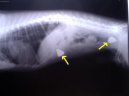

Cizí těleso s tenkém střevě - kameny.

Kostní trus v sestupné části tlustého střeva.